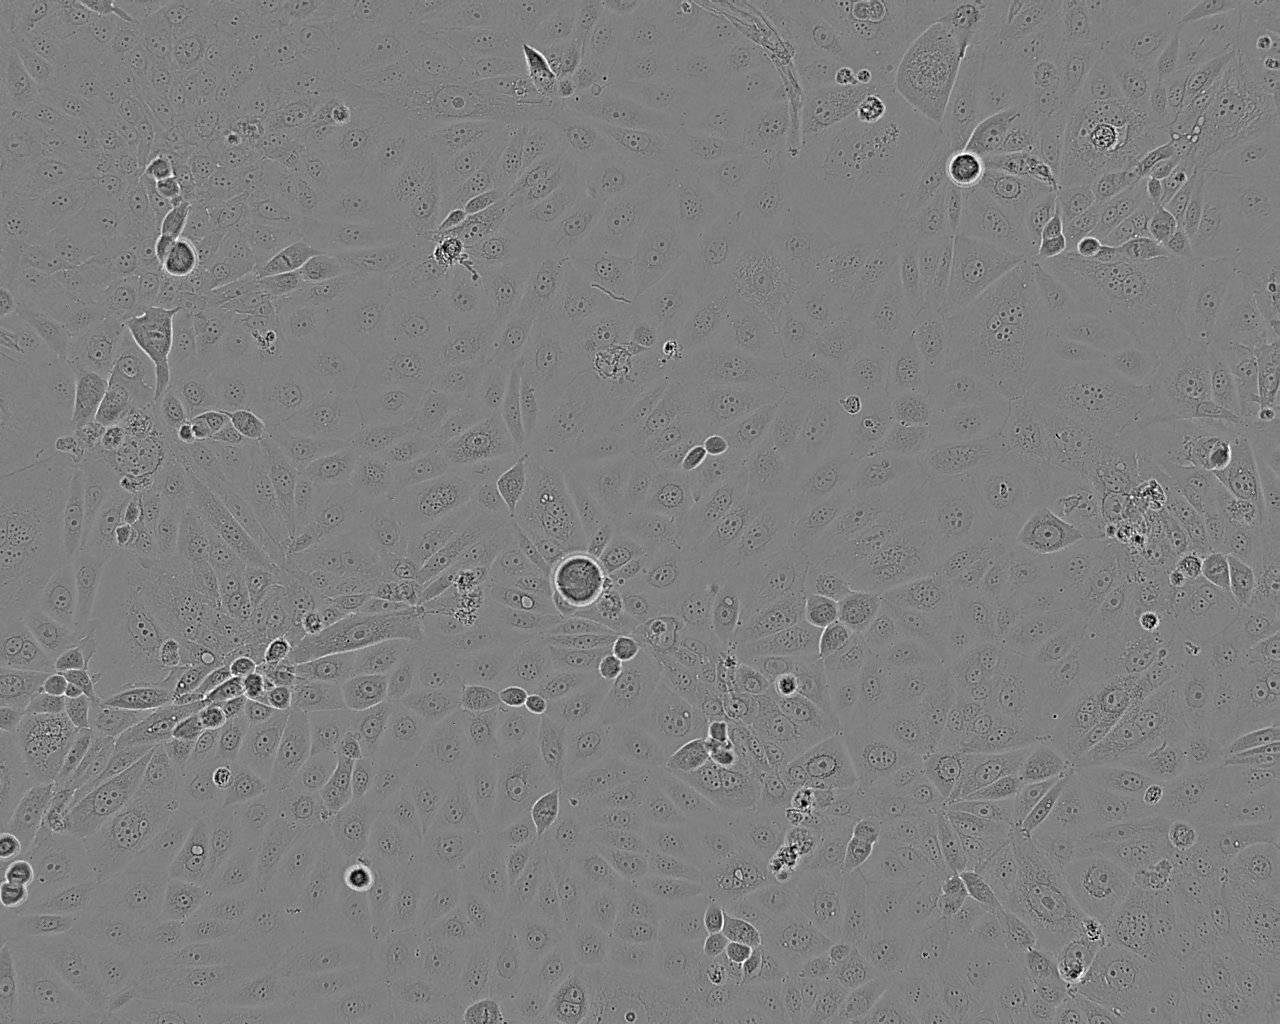

Derived from a grade 4 transitional cell carcinoma of the bladder of a 44 year old Caucasian male who had not received chemo or radiation therapy. The cells grow in soft agar, produce fibrinolytic activity and are tumorigenic in mice and hamsters.

Images